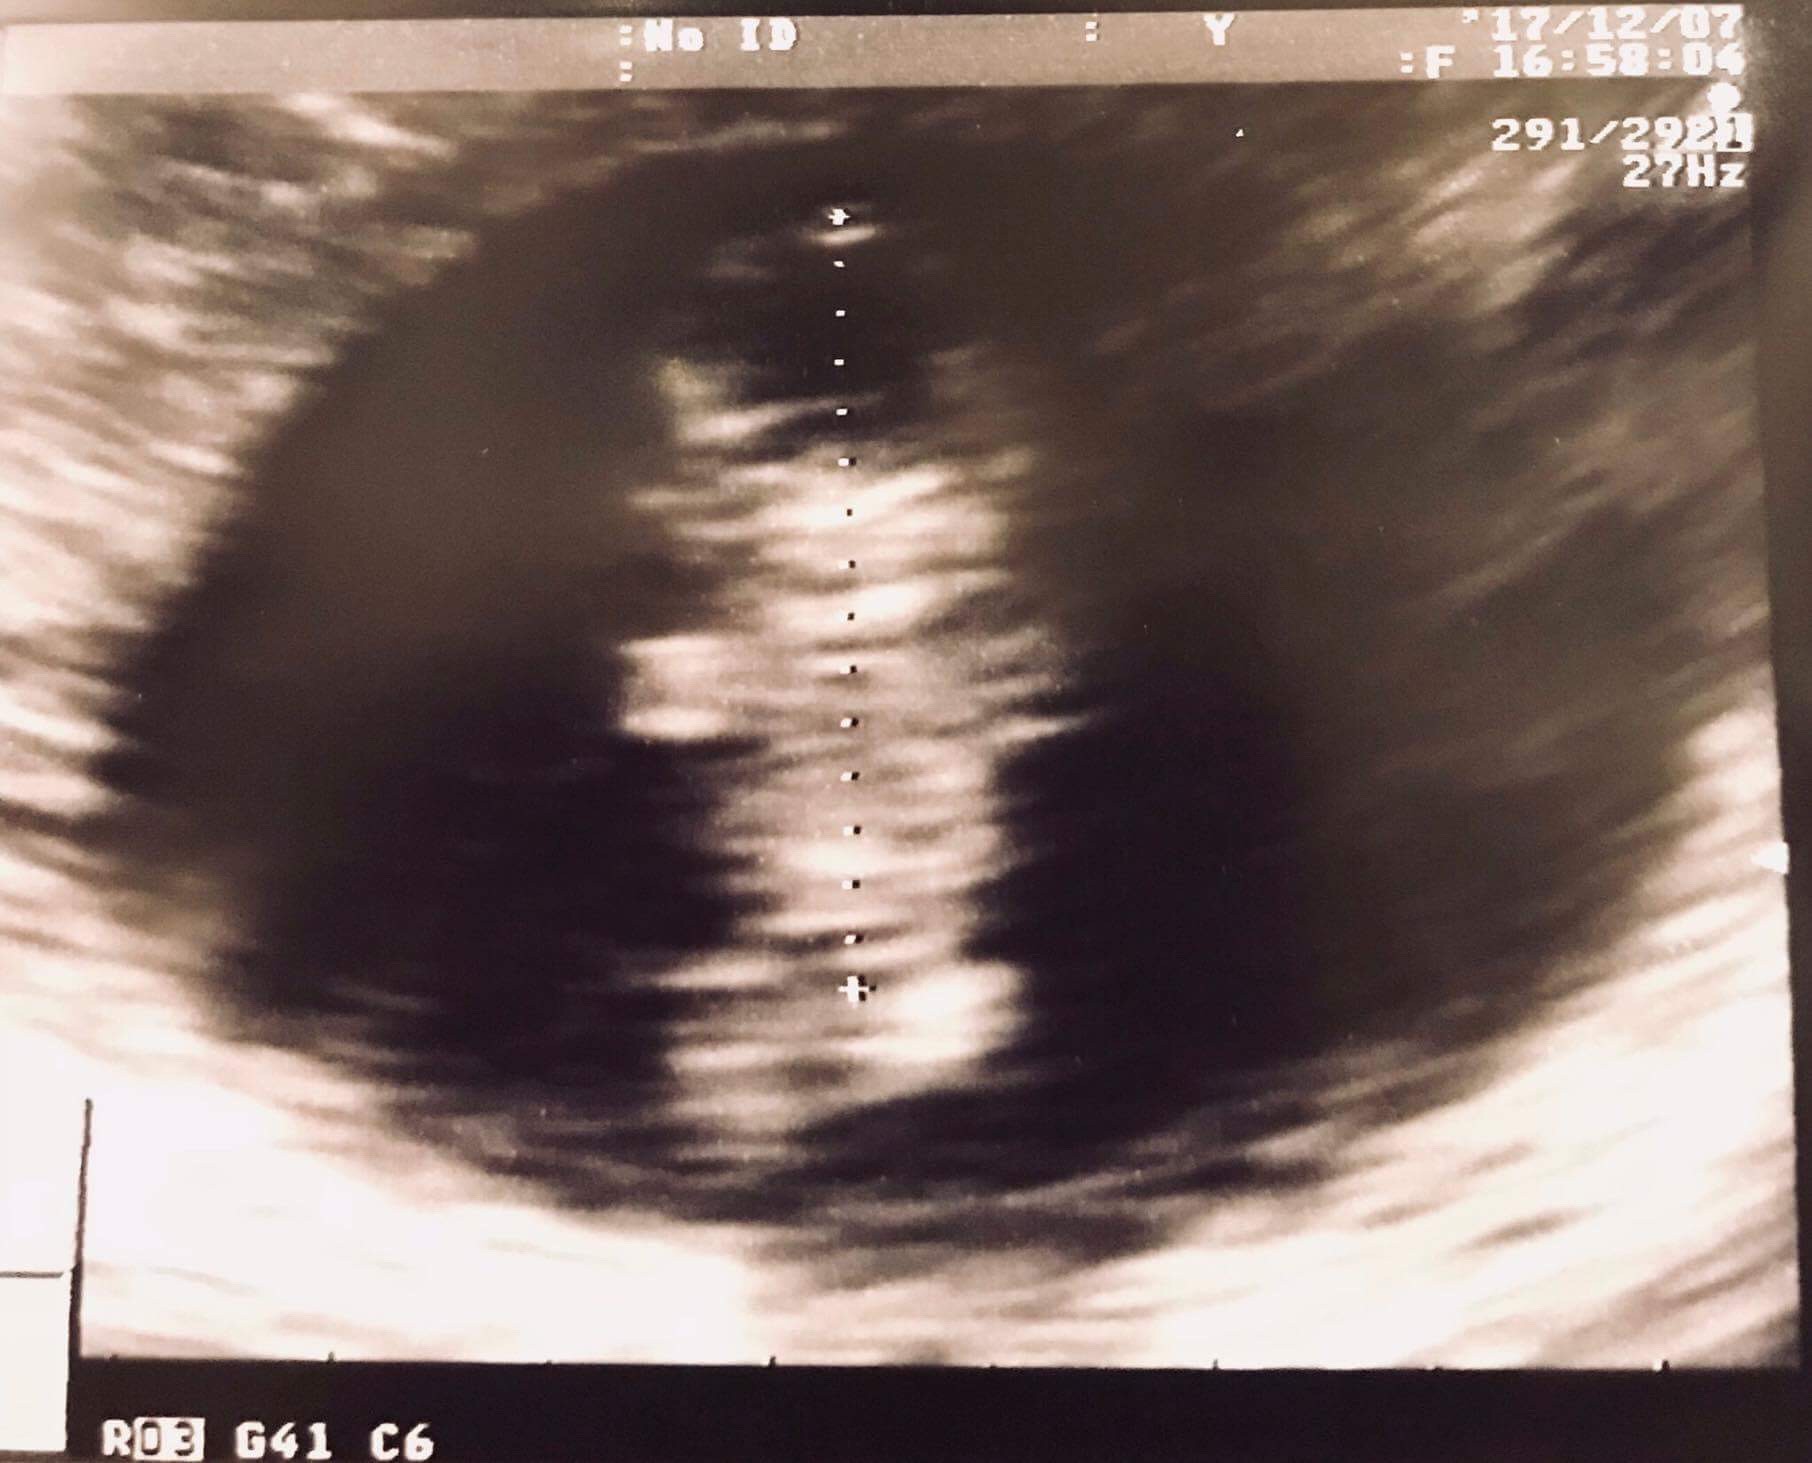

Hej, ja już po usg. Dzidzia ma 2,6 cmWidzieliśmy, jak macha nóżkami i rączkami

Jesteśmy zakochani.